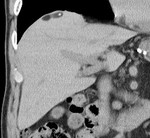

[画像診断]外科的肛門縁(Herrmann line)について 2011-05-26